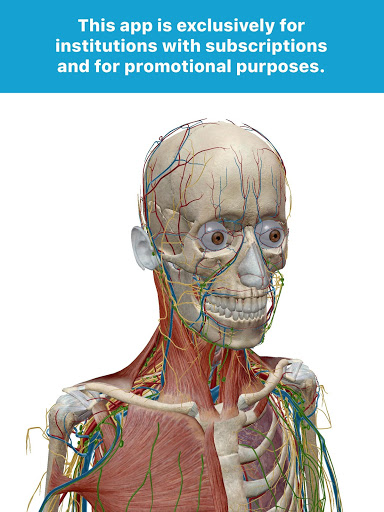

This version of Human Anatomy Atlas is for employees and students of institutions and organizations with a subscription. If you’re unsure whether this applies to you, we recommend you search for Human Anatomy Atlas by Visible Body to purchase the app.

More detailed gross anatomy

The male and female gross anatomy models have over a hundred new refinements!

Additional nerves, arteries, and veins in the head and neck region.